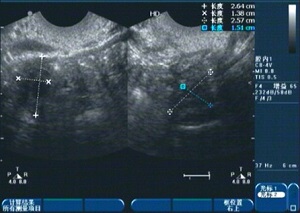

1、診斷:醫(yī)生會(huì)通過詢問病史、體檢及輔助檢查(如超聲檢查、激素檢測(cè)等)來確定診斷。